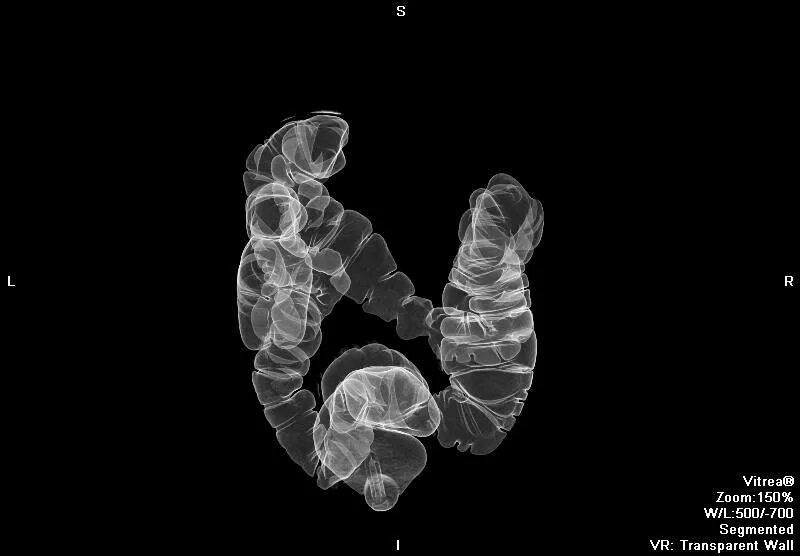

Обследование кт кишечника